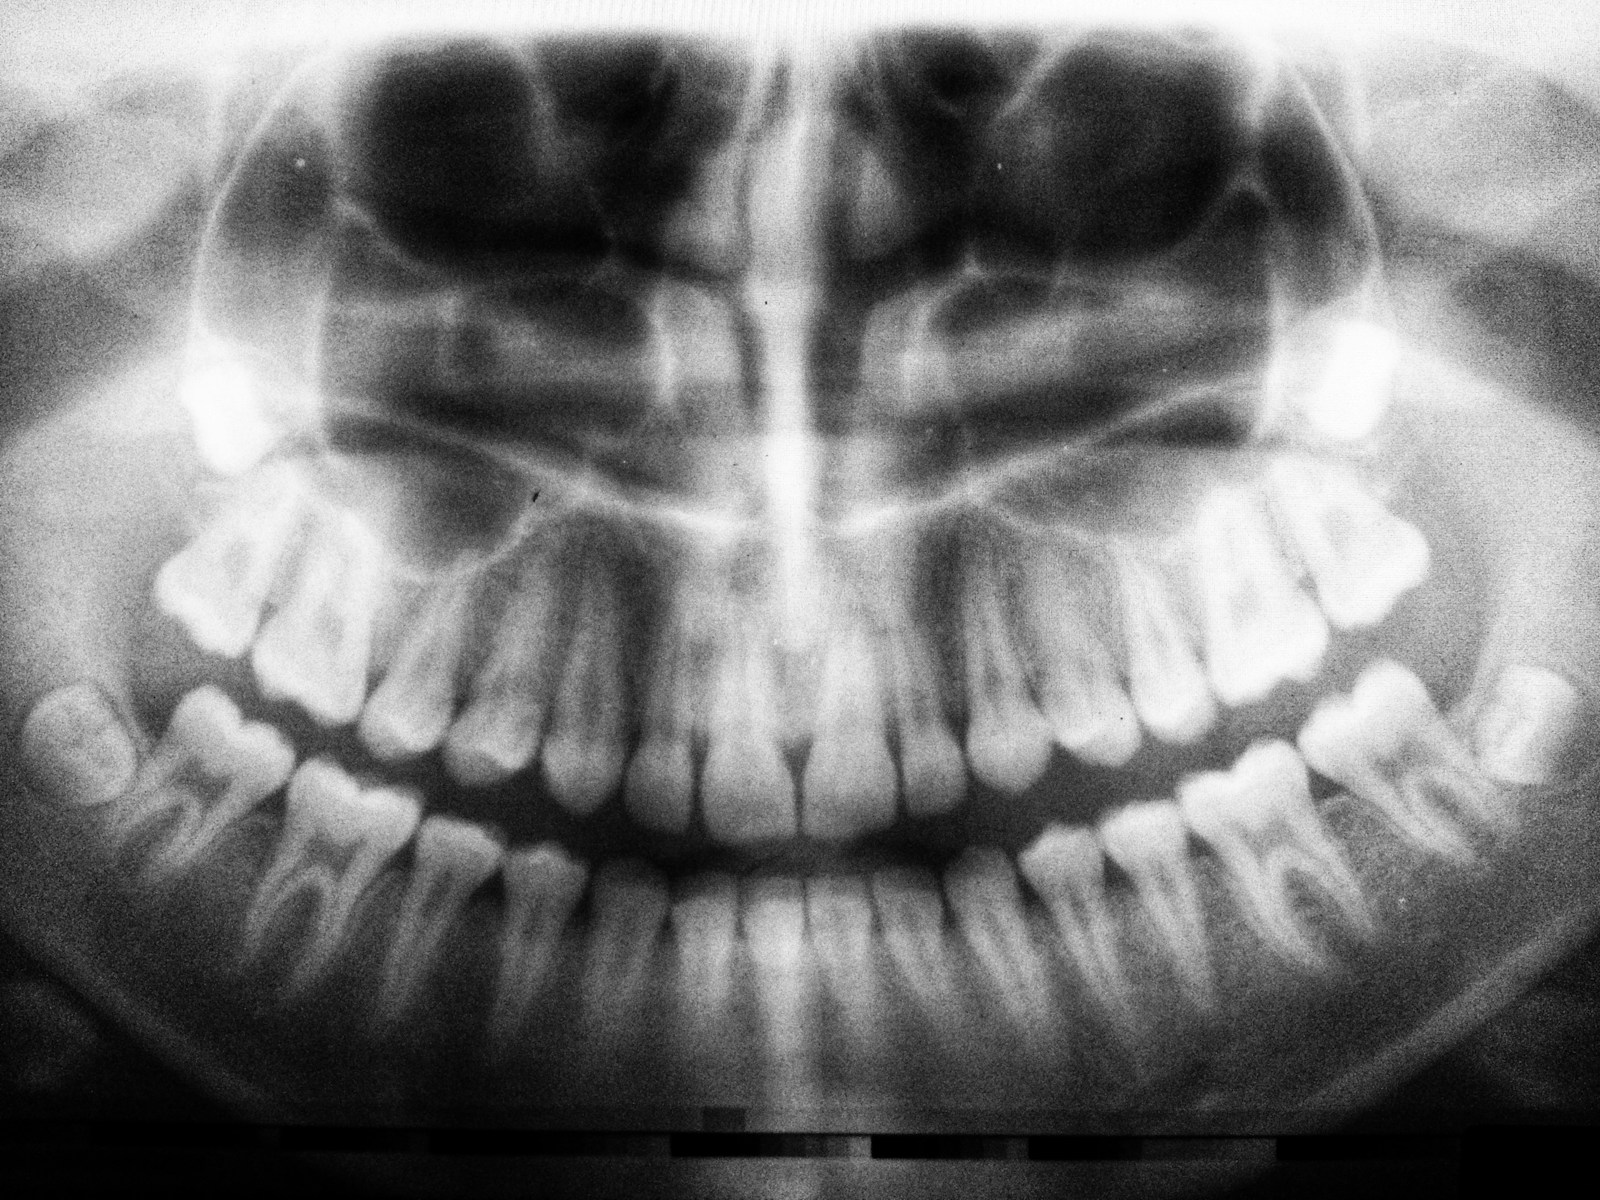

Upplever du ihållande tandvärk eller känslighet som inte går över? Det kan vara tecken på att du behöver en rotfyllning. På DermaDent i Sundbyberg utför vi rotfyllningar under mikroskop – en avancerad teknik som ger högre precision, bättre resultat och en betydligt mer skonsam upplevelse.

Vi på DermaDent erbjuder en överlägsen rotfyllningsbehandling tack vare vår avancerade mikroskopteknik. Vårt dentala mikroskop ger upp till 25x förstoring, vilket ger oss en exceptionellt hög precision under hela behandlingen.

Genom modern teknik och effektiv bedövning blir din behandling betydligt mer skonsam med minimalt obehag. Vår metod har en imponerande framgångsfrekvens på över 95% tack vare den avancerade tekniken vi använder.

Ja, alla tänder kan behandlas med mikroskopisk rotfyllning hos DermaDent i Sundbyberg. Mikroskopet är särskilt värdefullt för bakre tänder (molarer) som ofta har komplexa rotsystem med små kanaler som är svåra att lokalisera och behandla utan förstoring. För våra patienter i Sundbyberg och Stockholm är detta en stor fördel då det ökar chansen att rädda även de mest komplicerade tänderna.

Den största skillnaden är precisionen. Vid traditionell rotfyllning arbetar tandläkaren till stor del "blint" eller med begränsad syn. På DermaDent i Sundbyberg ger vårt operationsmikroskop upp till 25x förstoring, vilket gör att vi kan se detaljer som är omöjliga att upptäcka med blotta ögat. Detta resulterar i mer noggrann rengöring, bättre försegling och betydligt högre framgångsfrekvens. För patienter i Sundbybergsområdet innebär det färre komplikationer och längre hållbarhet.